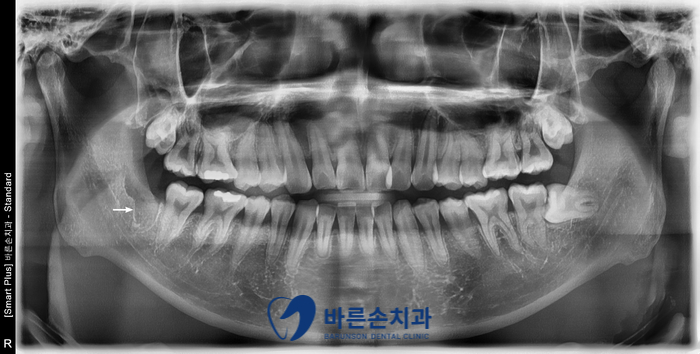

안녕하세요. <의정부 바른손치과>입니다.! 오늘은 사랑니 발치 증례를 보여드리도록 하겠습니다. 이 환자분은 20대 중반의 남성분으로 양쪽 아래 사랑니가 아프셔서 발치를 하러 저희 바른손치과를 찾아주셨습니다. 엑스레이 사진에서 보시면 양쪽 위 아래 사랑니가 모두 있고 왼쪽 아래 사랑니가 누워서 부분적으로 매복되어 있는 상태입니다. 구강 내 사진입니다. 좌우 모두 사랑니 머리가 일부만 구강내로 맹출해있습니다. 이런 경우 음식물이 끼기 쉽고, 칫솔로 제거도 쉽지가 않습니다. 그래서, 잇몸이 부어 피가 나고 아픈 경우가 자주 일어 날 수 있고 나아가 앞에 있는 치아 까지 썩게 할 수 있습니다ㅜㅜ 이런 경우엔 사랑니 발치를 통해 구강 환경 개선을 해야합니다!!! 사랑니 발치에 앞서 3D CT 촬영을 하였습니다. 사랑니의 형태와 위치, 아래턱뼈에 있는 하치조신경관의 해부학적 위치를 정확히 확인 후 발치에 들어갑니다. 오른쪽 아래 사랑니를 발치하고 엑스레이를 찍어 확인하였습니다. 왼쪽아래 옆으로 누워있는 사랑니도 발치를 하였습니다. 환자분께서는 문제를 일으키던 사랑니를 뽑으니 홀가분하고 시원하다고 하셨습니다.!! 약 일주일 정도 회복기간을 가지시면 사랑니 부위의 잇몸은 어느정도 아물게 됩니다. 사랑니 발치 더이상 두려워 하지 마시고 <의정부 바른손치과>에서 뽑으세요^^ |